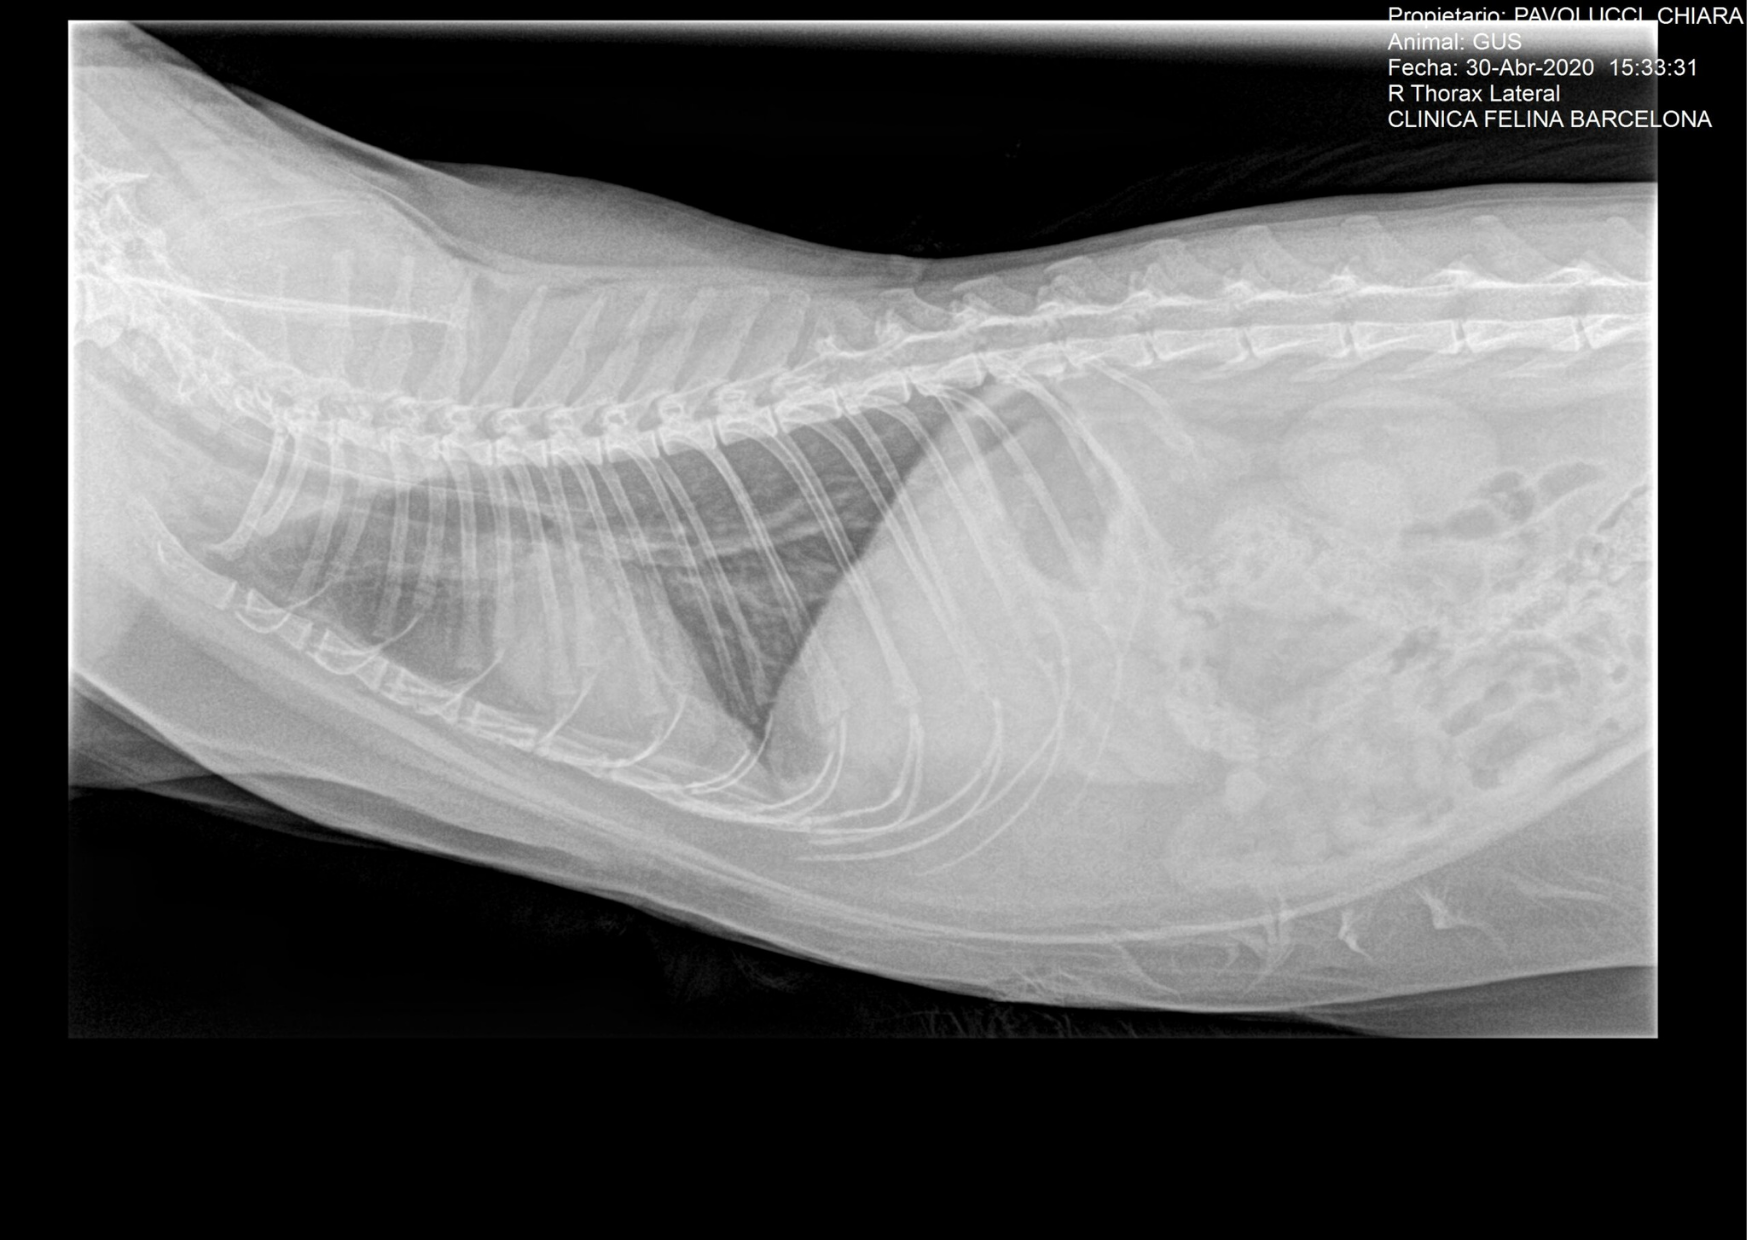

Caso clínico práctico. Dolor. Aerofagia y timpanismo. Diagnóstico Timpanismo En Gatos En los perros y en los gatos, se usa una amplia gama de formulaciones tópicas para el control de pulgas, piojos, ácaros y garrapatas. En animales de producción, la peritonitis se observa más frecuentemente en el ganado vacuno, menos en caballos, y raramente en. El timpanismo felino o flatulencias son originadas por un exceso de gas en el estómago o. Timpanismo En Gatos.